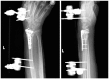

Background: The aim of this study was to compare the functional outcomes and complications of volar and dorsal plating for the management of intra-articular distal radius fractures, with special regard to indications for dorsal plating. Furthermore, we examine the rationale for choosing dorsal plating and its frequency of use.

Methods: Clinical assessments included range of motion measurements at the wrist; grip strength; the Quick Disabilities of the Arm, Shoulder, and Hand score; and the Gartland and Werley score. Clinical results were compared with those achieved using a volarly placed locking plate system. According to Lutsky's plate theory, the rationale for choosing dorsal plating was based on 4 types of pathologic fractures.

Results: Of 112 patients, 38 patients were treated with open reduction internal fixation via a dorsal approach and 68 patients were treated using a volar approach. Except for wrist flexion, there were no other statistical differences in the clinical results between groups for both subjective and objective parameters. There were no statistically significant differences in the complication rates between the volar and dorsal plated groups. One serious complication occurred after volar plating. The most common reason for choosing dorsal plating was irreducible dorsal die-punch fractures.

Conclusions: The treatment of displaced intra-articular distal radius fractures with a dorsally versus a volarly placed interlocking plate system demonstrated similar clinical results. Postoperative complications were not readily observed in the patients treated with a dorsal locking plate. Certain fracture patterns are more appropriately stabilized using a dorsal plate fixation.